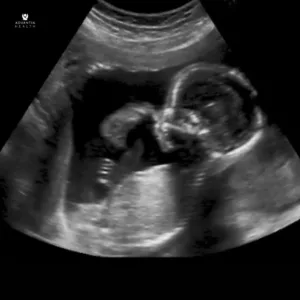

Transforming women’s health and wellness education with our providers’ expertise. Covering gynecology, obstetrics, mental health, and more – beyond the boundaries of the exam room.